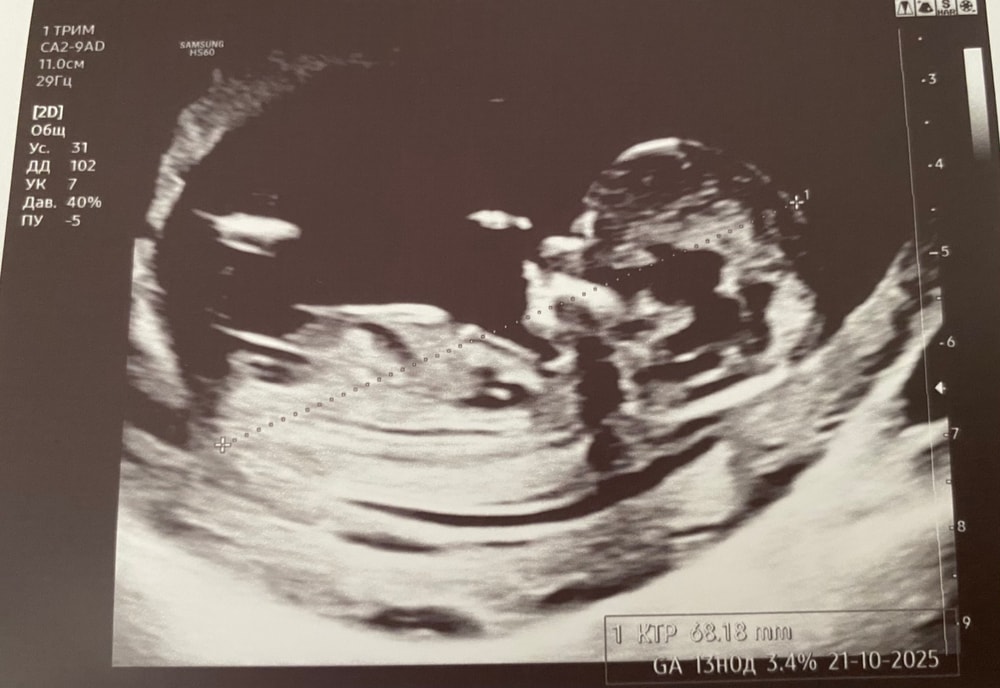

Анастасия 8 месяцев 1 скрининг Как думаете , кто?🩵🩷 Посмотрите еще 20 записей на эту тему Лучший ответ Наталья Где-то смотрела, что если пипка горизонтальная, то девочка. Вертикальная, то мальчик)). С учётом этой теории, по мне, у вас девочка)) 15.04.2025 Ответить Отменить Ответить Анастасия Девочка 15.04.2025 Ответить Екатерина Лучшие спросить узиста. Здесь не факт, что есть лабок на срезе узи 15.04.2025 Ответить Анастасия Девочка) 15.04.2025 Ответить Виктория Девочка 15.04.2025 Ответить Динамика мама check (8-15дпо) Чаты Беременных Выберите чат: Январята-2026 Февралята-2026 Мартята-2026 Апрелята-2026 Майчата-2026 Июнята-2026 Июлята-2026 Августята-2026